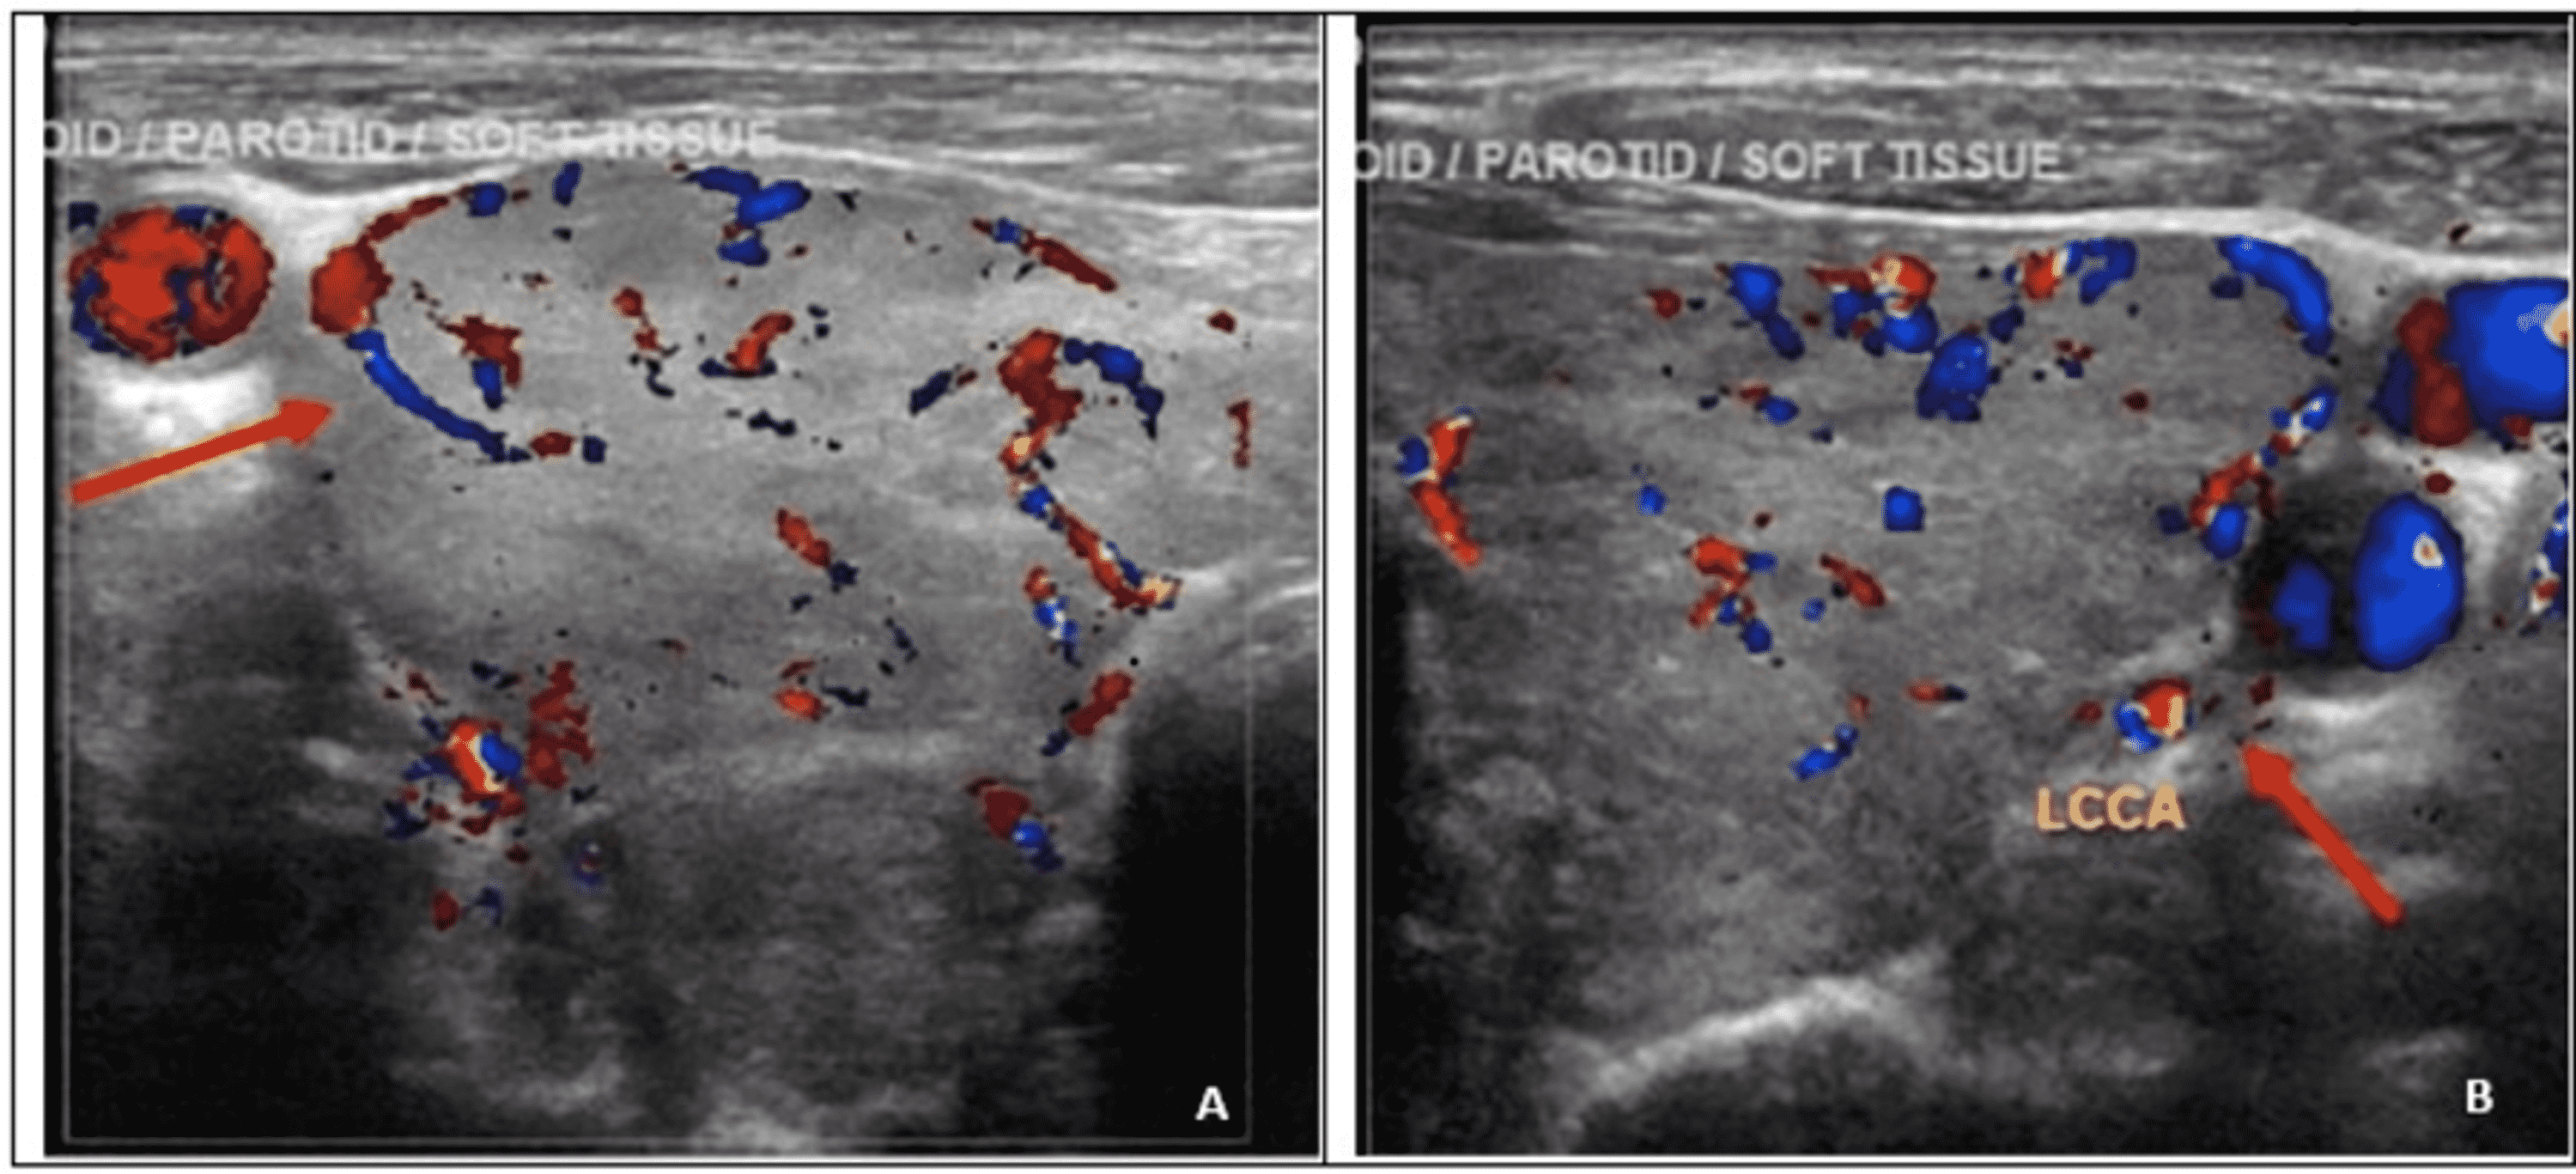

The Diagnostic Value of Ultrasound in Medullary Thyroid Carcinoma A Thyroid Gland Echotexture this study aimed to determine the malignancy risk of thyroid nodules according to their echotexture and degree of. Hashimotos’ and graves’ disease glands exhibit hypoechogenicity on ultrasound (us). thyroid glands with heterogeneous echogenicity showed significantly lower specificity, ppv, and. prominent reactive cervical nodes may be present, especially in level vi, but they have normal morphologic features ref.. Thyroid Gland Echotexture.

Longitudinal ultrasound of the left thyroid lobe. (A) Almost 30 minutes Thyroid Gland Echotexture prominent reactive cervical nodes may be present, especially in level vi, but they have normal morphologic features ref. Hashimotos’ and graves’ disease glands exhibit hypoechogenicity on ultrasound (us). this study aimed to determine the malignancy risk of thyroid nodules according to their echotexture and degree of. decreased echogenicity of the thyroid gland on us is associated with. Thyroid Gland Echotexture.